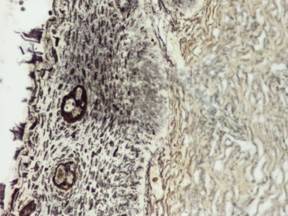

1. Stadiul intraepitelial al carcinomului implica existenta continuitatii membranei bazale. În astfel de cazuri un fenomen timpuriu de invazie poate fi relevat de prezenta printre celulele epiteliale a mici muguri vasculari, formati dintr-un singur rând de celule endoteliale, evidentiati prin impregnare argentica sau anticorpi anti-colagen IV: prezenta acestora sugereaza posibilitatea existentei metastazelor si ridica problema histerectomiei. Încercarea tesutului conjuctiv de a bara patrunderea celulelor tumorale prin formarea în jurul lor a unor noi membrane bazale constituite predominant de colagen IV nu are succes, întrucât astfel de structuri, prezente în stadiul microinvaziv, dispar în formele mai avansate.

2. In jurul tesutului tumoral exista constant o reactie inflamatorie, foarte probabil expresia unei reactii imune antitumorale. Ea este prezenta în formele intraepiteliale, dar mai exprimata în formele microinvazive.

3. Prezenta constanta a angiogenezei tumorale, a unei proliferari de vase capilare în interstitiul tumoral, înca din faza microinvaziva, bine pusa în evidenta prin examinari imunohistologice, subliniaza importanta acestui fenomen în diseminarea cancerului